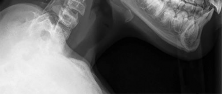

A 12-year-old obese male presents with left groin pain and an altered gait. Based on the presumed diagnosis of slipped capital femoral epiphysis (SCFE) shown in the representative radiograph, which of the following is the primary blood supply to the femoral head that is at highest risk for iatrogenic injury during percutaneous in situ pinning if the pin is placed in the posterosuperior quadrant?

The primary blood supply to the capital femoral epiphysis in children over the age of 3 is the posterosuperior retinacular vessels (lateral epiphyseal artery), which are terminal branches of the medial circumflex femoral artery (MCFA). During in situ pinning for SCFE, placement of the pin in the posterosuperior quadrant of the femoral neck/head places these extracapsular vessels at extreme risk of injury, potentially leading to avascular necrosis (AVN). Pins should ideally be placed in the center-center position to minimize this risk.